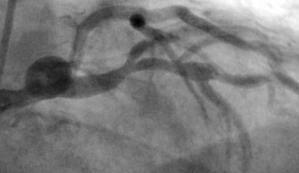

2 x Stent in RCA (Hinterwandarterie); Verschluss eines kleinen Seitenastes (idR ohne klinische Folgen)

2 x Stent in RCA (Hinterwandarterie)